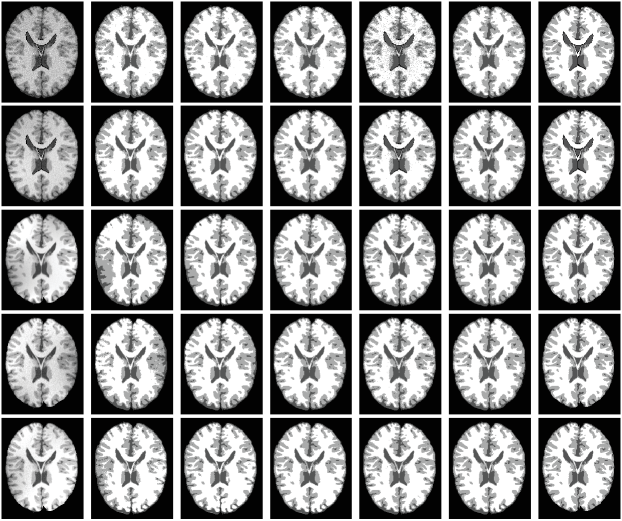

4.2 Evaluation on pubic image repositories

In this subsection, we evaluate effectiveness of the proposed model quantitatively on one simulated MR dataset and one real MR image dataset. The first one consists of 9 cases of MR images with three different levels of noise and intensity inhomogeneity, respectively. Resolutions of the images are with 1 mm in-plane pixel size and 1 mm slice thickness. For more information about the dataset, interested readers are referred to the website http://brainweb.bic.mni.mcgill.ca/brainweb/ and the reference [33]. To construct a much more challenging dataset for segmentation methods, three more levels of non-linear intensity inhomogeneities are added to the original image with noises. Therefore, there are totally 18 image cases for the first image dataset. The second image set is known worldwide as the Internet Brain Segmentation Repository (IBSR) which contains 18 cases of T1-weighted brain MR image cases with skull-removed masks and manually-guided expert segmentation results. Resolutions of the images are all . Interested readers are referred to https://www.nitrc.org/projects/ibsr for detail. Note that for each image case, the segmentation task is to extract white matter (WM), gray matter (GM), and cerebrospinal fluid (CSF) from the background. As intensities of the background are all zero for the images, two level set functions are used to partition the images into three regions that is and . To compare performance of the proposed model with state-of-the-art models like CV, LIC, and LINC on these image datasets, we first extend the comparable models to three phase (matlab codes will be released on our personal homepage if this paper got published). We then define membership functions , , and to represent WM, GM, and CSF, respectively. For a fair comparison, we first extend comparison models to three phase and then use the same parameter set and the same strategy to initialize the level set functions for all the comparison models. The initialization strategy is that areas separated by a predefined threshold are adopted to initialize by considering the areas as inside and outside of the zero level contour. Areas separated by another predefined threshold are adopted to initialize the level set function . The thresholds are adaptively defined as 0.8 and 0.3 times of maximal intensity of pending to be segmented images. We have to point out that the proposed model is robust to initialization which will be discussed in section 5.3. Note that we applied the proposed model and comparable state-of-the-art models only on image slices that really contain WM, GM, and CSF.

4.2.1 Qualitative comparison

Segmentation results of the proposed model with three state-of-the-art level set models, i.e., CV, LIC, and LINC, and the global clustering based MICO on the -th slice of selected brainweb cases and the -th slice of selected IBSR image cases are given in Fig. 8 and Fig. 10. The corresponding bias estimation and correction results are given in Fig. 9 and Fig. 11, respectively. The reason we select these image is that they are the most noisy and biased and they are therefore challengeable. It can be seen that 1) the proposed model is much more robust to noises and bias fields and 2) segmentation results of the proposed model are much more close to corresponding ground truth. Due to potential relatedness of the proposed model to MICO, it is necessary to compare them qualitatively and quantitatively, beside describing theoretical differences as given in Remarks 8-10. It can be obviously seen that 1) MICO is sensitive to noise, especially as shown for the first two images of Fig. 8 with 9% and 6% noises to the brightest tissue and 2) MICO prefers to provide high biases at image centres which can be seen from Fig. 10 and especially for the first image in Fig. 8 with no intensity biases actually. But bias fields estimated by the proposed model are much more matching with the actual situation and the bias estimated is almost a constant for the first image in Fig. 8 which is not corrupted by inhomogeneities in fact. Quantitative evaluation will be given in section 4.2.2.

Orig CV LIC LINC MICO IEOPF GT

Orig Bias Corrected

LIC LINC MICO IEOPF LIC LINC MICO IEOPF